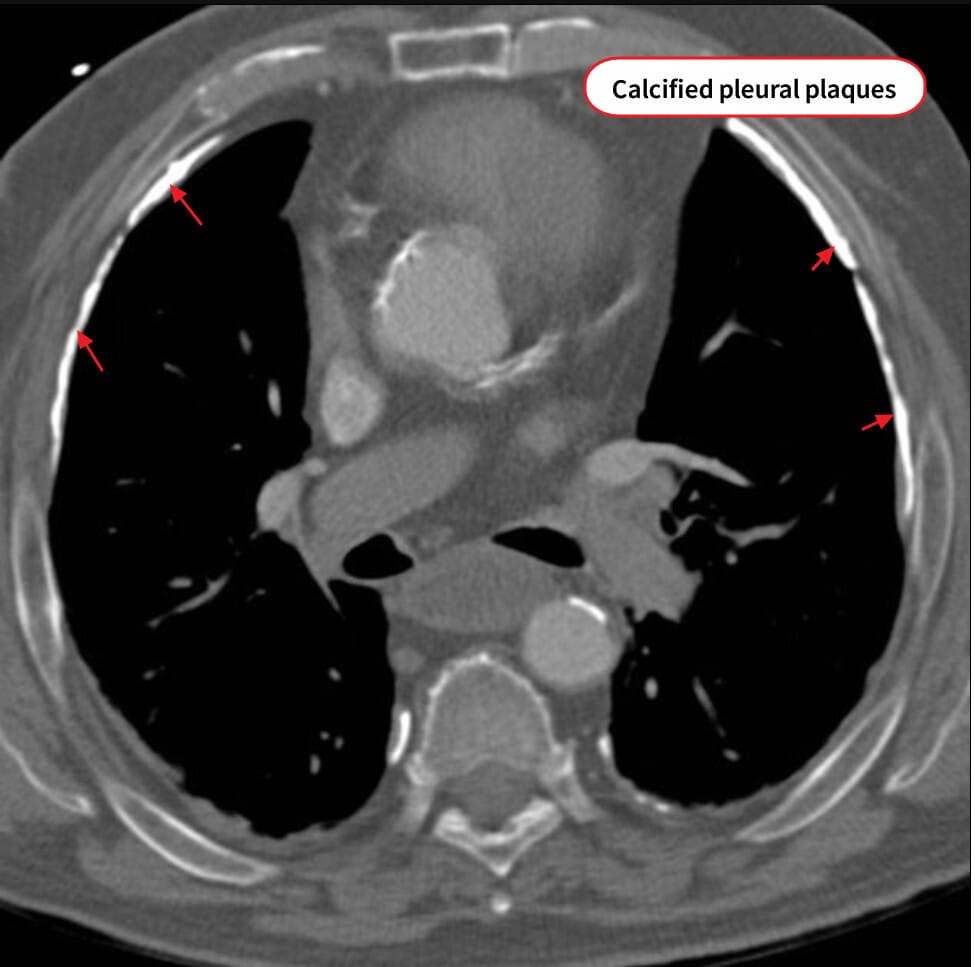

석면폐증 (Asbestosis)

정의

– 장기간 석면 섬유 흡입으로 폐간질 섬유화가 진행하는 직업성 폐질환

– 폐암 및 악성 중피종 위험 증가와 연관

진단

– 직업력 확인과 흉부 CT에서 기저부 간질성 음영과 흉막 석회화 확인

Calcified Pleural Plaque

: 흉막에 석회화가 발생하여 관찰됩니다.

CT에서는 이렇게 관찰됩니다.

– 폐기능검사에서 제한성 장애; DLCO 감소; 암 발생 여부 확인

– 폐암 감별 위해 조직검사 고려 –석면 소체 (Asbestos bodies)